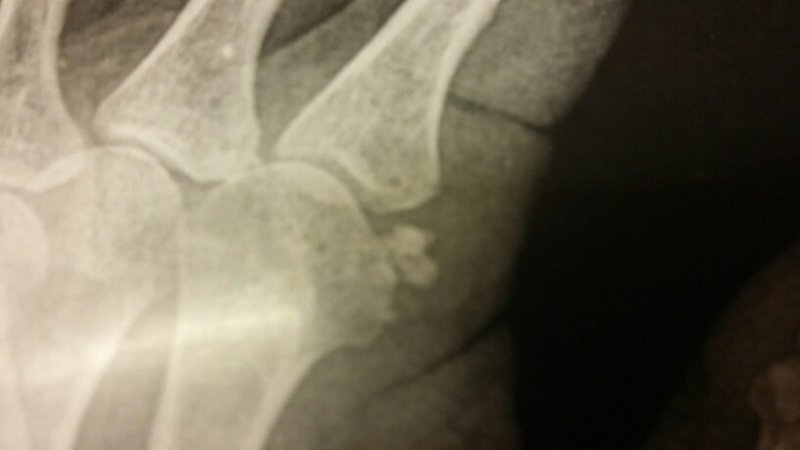

J'en suis à la 3 eme crise en 8 mois et cette fois...ça a été bien pire puisqu'au bout de 4 jour de gêne disons "modérée" comme les 2 premières fois, et malgré un traitement anti inflammatoire l'articulation est devenue rouge chaude très enflée et douleur+++ même au repos ( insomniante) Tableau de "pseudo-goutte"

J'ai donc vu en urgence dès le lendemain un collègue rhumato qui m'a bien examinée, a éliminé les choses embêtantes ( polyarthrite rhumatoïde ou arthrose destructrice par exemple) et confirmé un diagnostic d'arthrite microcristalline à hydroxy-apatite ( joli, n'est-il pas? on hésite entre la médecine et la minéralogie... :lol: )

IL était tout content devant l'écho, et moi presque fière d'être un cas d'école assez rare dans cette localisation.

Le piano a pu révéler le problème, mais n'est pas coupable. Ouf!

Les radios confirment. On voit très bien le gros paquet de calcifications "mûriformes" ( a droite, il y en a peut-être une aussi, mais toute petite, et j'espère qu'elle se tiendra tranquille. Et dans l'ensemble les radios ( 2 mains et poignets) me paraissent pas mal, très peu d'arthrose. Je vais donc pouvoir continuer

Les pronostic est assez bon, bien que....çà puisse récidiver encore! A priori pas d'infiltration, encore moins de chirurgie avec cette localisation...Juste de la patience, des anti-inflammatoires et de la glace...

hydroxy apatite.jpg

hydroxy apatite.jpg (26.59 Kio) Vu 2640 fois